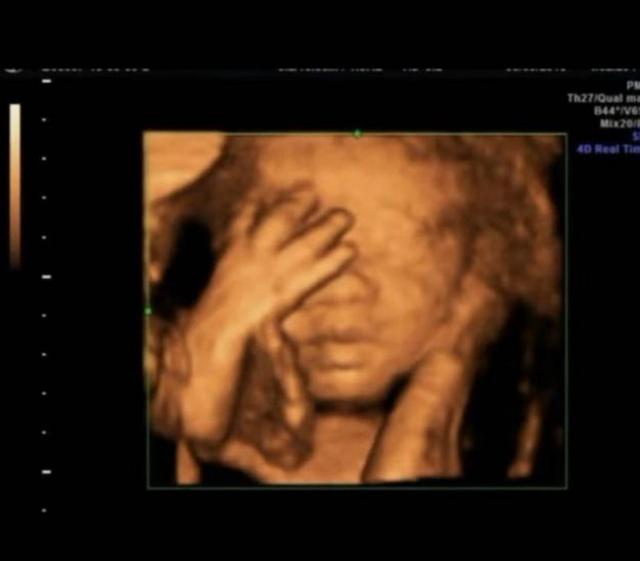

原來小夏每一次做四維她都把胎兒在子宮裡的情況照下來,加上這次正好四次,而每次四維顯示出來的胎兒都在子宮裡擺出不同姿勢和手勢,但是連在一起就非常像小朋友「數數」,因為四次四維圖象連在一起胎兒的手勢正好是數字「1234」。

有了這個驚奇發現,小夏立刻問醫生是怎麼回事,醫生打趣道「看來這是娘胎裡的學霸啊」不過後來醫生解釋了,胎兒在子宮裡是運動的,擺出什麼樣的姿勢和手勢並不能說明什麼問題,因為胎兒自己在子宮裡也很忙碌的。

子宮裡黑乎乎的,胎兒周圍都是羊水,除了臍帶什麼都沒有,胎兒怎麼玩遊戲呢?其實胎兒的玩具就是臍帶,就是因為繞來繞去才有了臍帶繞頸,還有的胎兒會玩自己的手指,所以小夏看見自家寶寶在「數數」可能也是胎兒自娛自樂呢!